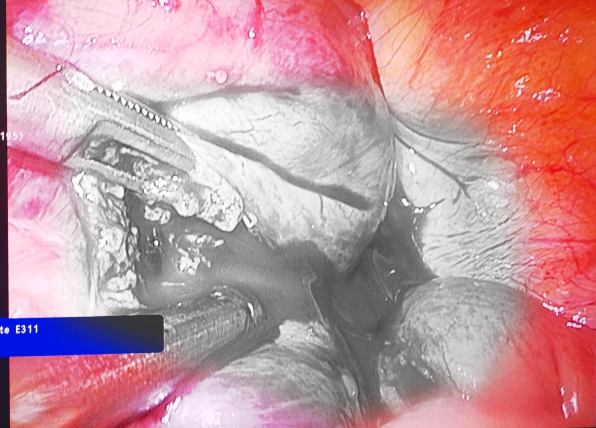

腹部疼痛不止,检查发现大出血,罪魁祸首竟然是“它”?

如今,谢女士的生命体征已逐渐平稳,从手术室中的生死竞速,再到术后床旁的细致守护,这场跨越妇科、普外科、麻醉科的生命保卫战,是我院多学科协作的成功案例。

子宫内膜息肉的宫腔镜治疗,子宫肌瘤、卵巢囊肿、异位妊娠的腹腔镜治疗,经腹输卵管吻合术,宫颈疾病的锥切手术(Leep刀、冷刀),盆腔脏器脱垂的治疗,对产科头位难产的处理有独到的见解。

腹腔镜下肝胆、胃肠、疝等微创手术及肛肠科常见疾病的诊治。